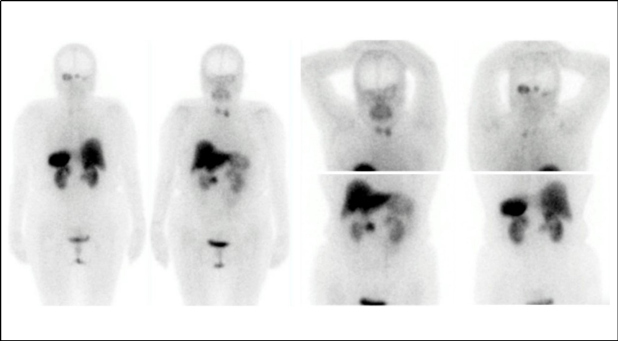

En las imágenes planares se observan múltiples áreas de captación anormal en la fosa posterior y en el aspecto lateral del hilio renal derecho (fig. 1). Se identifican tres lesiones cerebelosas con componente sólido realzante y quístico, altamente vascularizadas, que presentan aumento de perfusión y generan edema extenso obliterando el cuarto ventrículo, consistentes con hemangioblastomas (fig. 2). Existe otra lesión que genera invasión ósea de la mastoides con compromiso del oído interno; en la RM es isointensa e hiperintensa en las secuencias T1, hiperintensa en las secuencias T2, con captación del medio de contraste, por tumor del saco endolinfático (fig. 2). En la valoración de la cavidad abdominal se detecta una lesión sólida en la cabeza/proceso uncinado del páncreas, hipodensa respecto al resto del parénquima, compatible con tumor neuroendocrino (fig. 3).